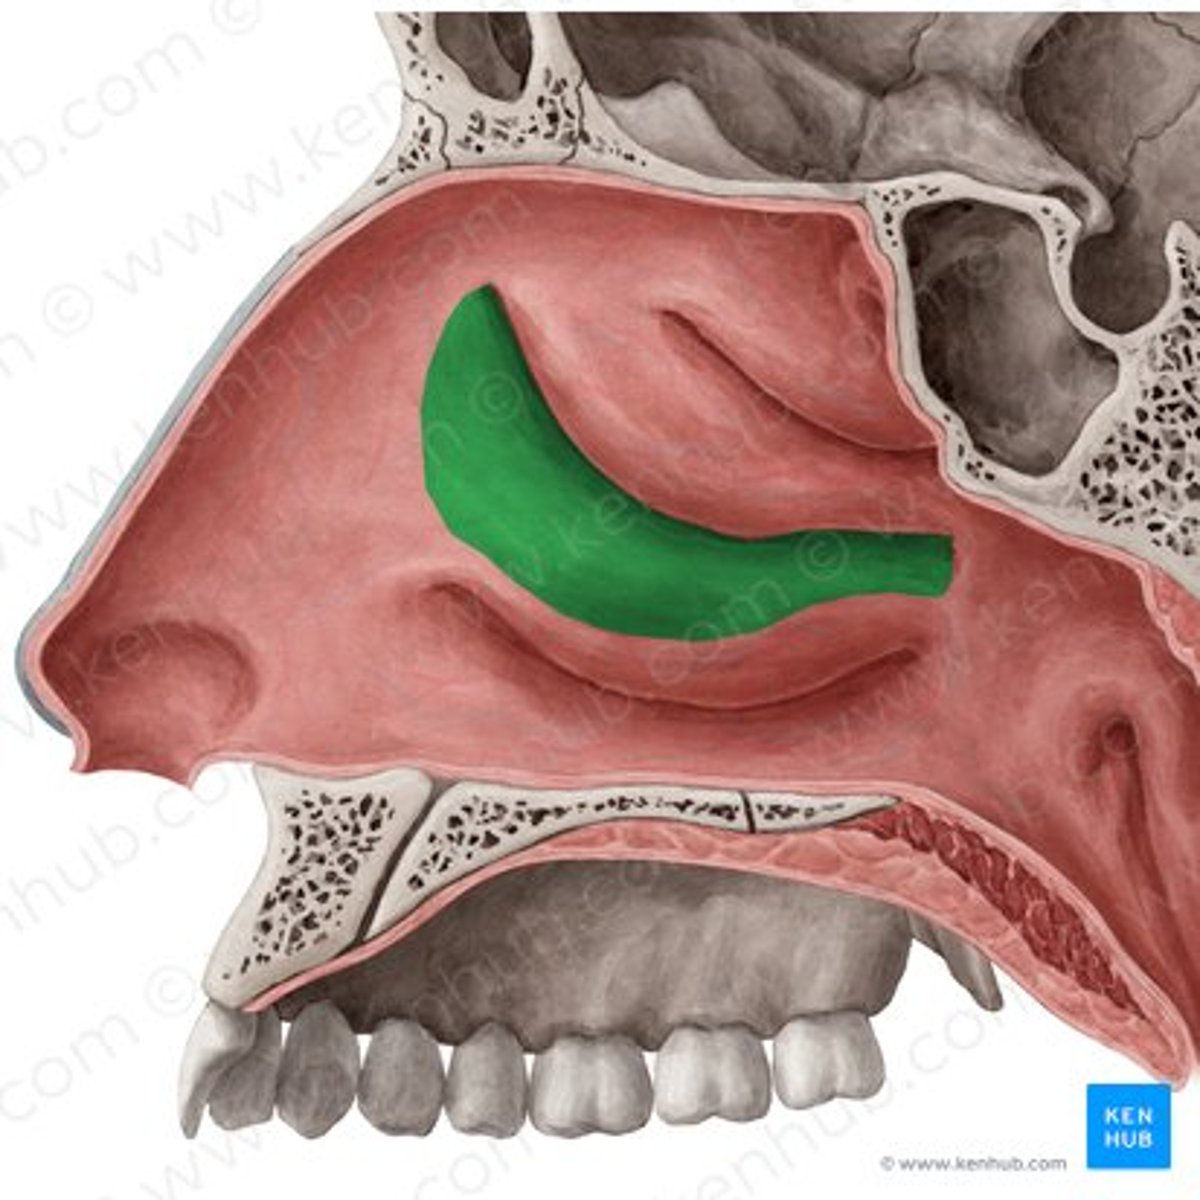

superior meatus

middle meatus

inferior meatus

inferior nasal concha